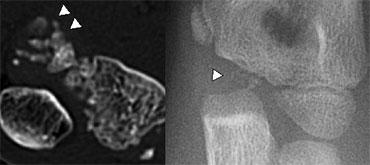

The Ròng rọc (Trochlea) có hai hoặc nhiều trung tâm cốt hóa, có thể tạo ra hình ảnh ròng rọc bị phân mảnh.

Trên hình chiếu bên, các điểm cốt hóa ròng rọc có thể chiếu vào trong khớp.

Không nên nhầm lẫn chúng với các dị vật tự do trong khớp (mũi tên).